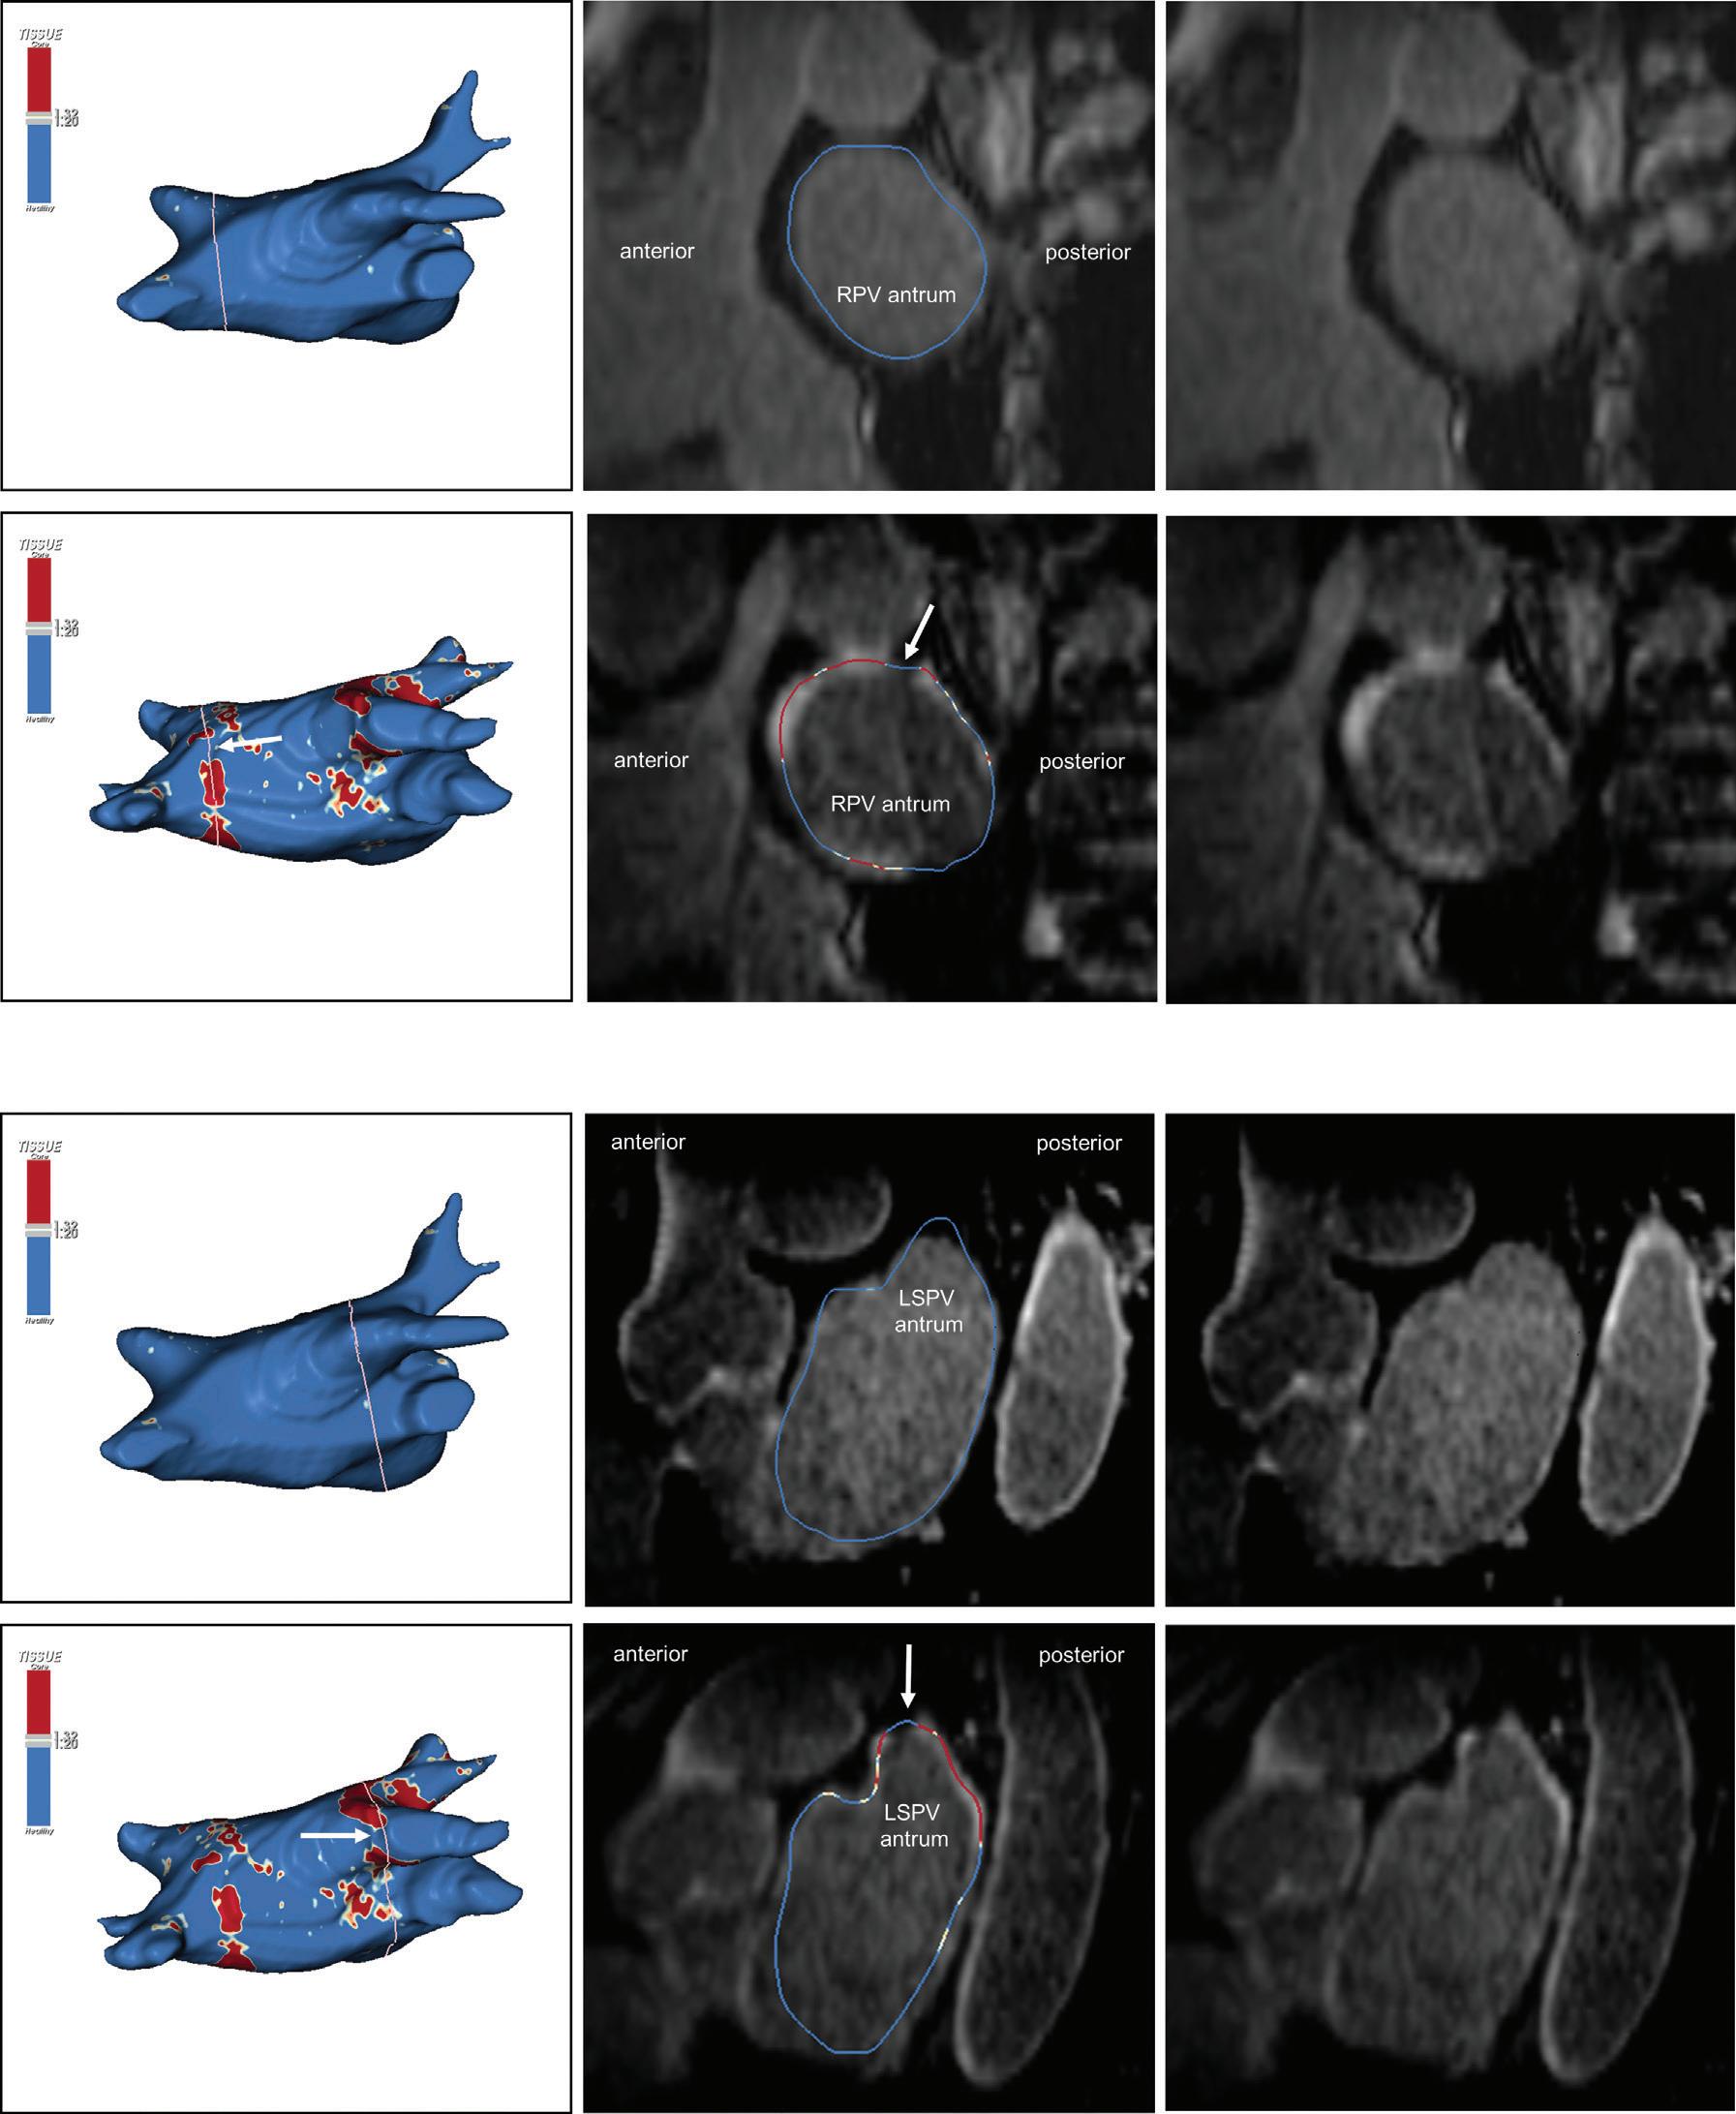

Figure 1: Ablation-induced Late Gadolinium Enhancement After Pulmonary Vein Isolation

Preprocedural LGE-MRI (1 day before PVI) Post-ablation LGE-MRI (3 months after PVI) LIPV RIPV LSPV RSPV LIPV RIPV LSPV RSPV Postero-anterior view Postero-anterior view

Left: 3D reconstruction of the LA with colour-coding based on image intensity ratios with thresholds for dense scar (red >1.32) and border zone (yellow 1.2–1.32), using ADAS 3D software (Adas3D Medical). Blue lines indicate the plane of the LA slices on the right. Middle: Overlay of the T1-weighted images with the LGE colour-coding described above. White arrows point to local ablation-induced LGE lesions. Right: T1-weighted LGE-MRI slice depicting the LA with evident LGE of PV ostial walls. LA = left atrium; LAA = left atrial appendage; LGE = late gadolinium enhancement; LIPV = left inferior pulmonary vein; LSPV = left superior pulmonary vein; PV = pulmonary vein; PVI = pulmonary vein isolation; RIPV = right inferior pulmonary vein; RSPV = right superior pulmonary vein.